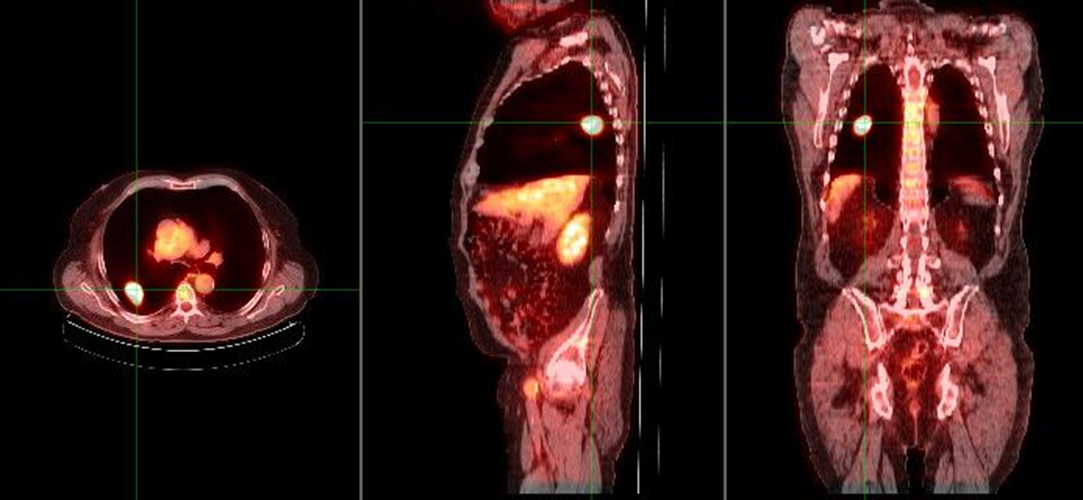

what does this image show

malignant single pulmonary nodule

benign single pulmonary nodule

what does this image show if the chest x-ray demonstrated a nodule in the right lung

increased metabolic activity indicative of malignancy

single pulmonary nodule (SPN)